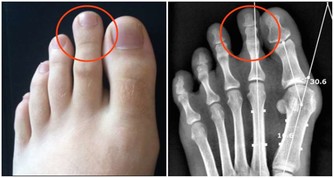

8保護骨骼

我們都知道很多人一上了年紀都容易得骨質疏鬆症,是因為體內鈣質流失。那麼怎樣有效防止鈣質的流失呢?一種簡單有效的方式就是運動出汗,出汗有利於鈣質的有效保留,防止體內的鈣質隨尿液排出,預防骨質疏鬆。